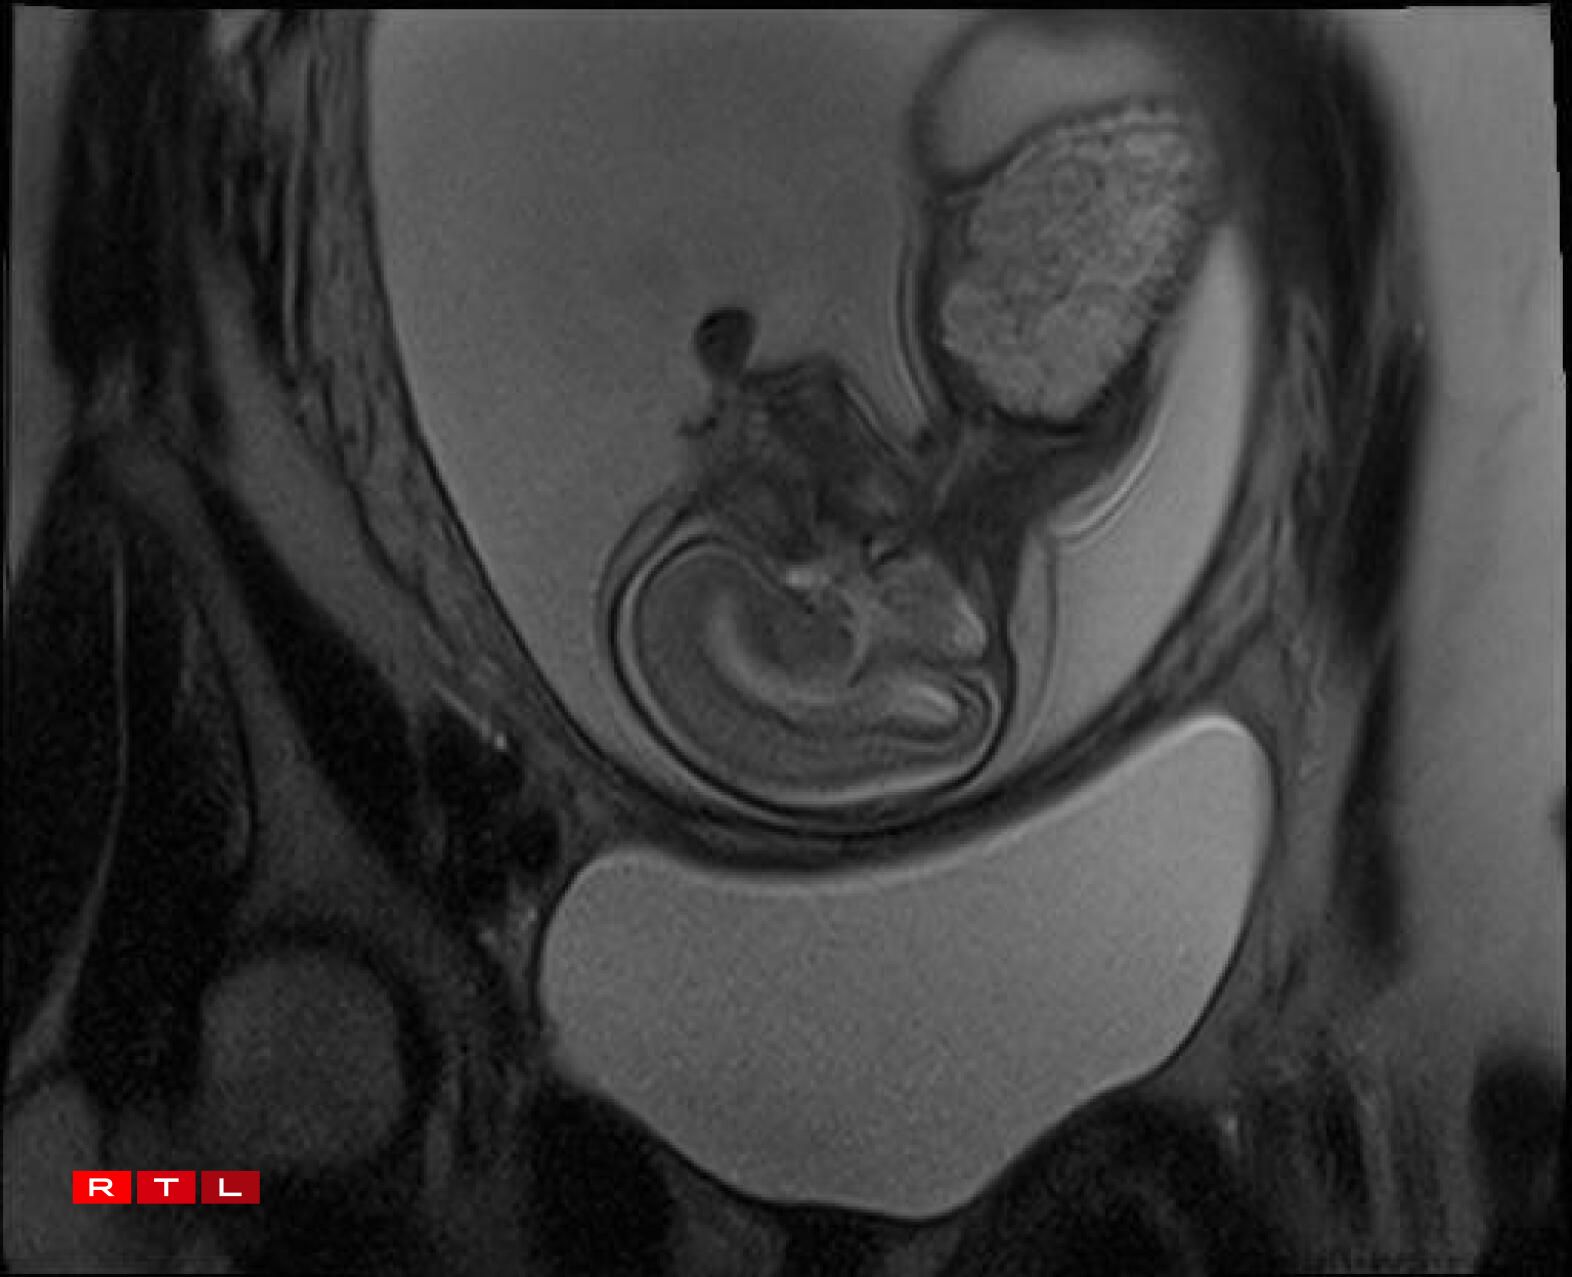

Lis was therefore referred to the Centre Hospitalier de Luxembourg (CHL), where further examinations led to a diagnosis. Noa was found to have a congenital pulmonary airway malformation (CPAM). Doctors explained that a large mass of cysts had formed in his chest, compressing his heart and disrupting his circulation. This, in turn, caused the fluid retention observed during the initial scan.

In Noa’s case, the CPAM was caused by a malformed aorta: a blood vessel had branched toward the lungs and was feeding the cysts. The condition is known as a sequestration. Professor Kohl proposed the following intervention:

“He would go through my abdomen with two small incisions to reach the amniotic sac, then pass through Noa’s chest to the heart, where he would cauterise the blood vessel that was feeding the cysts using a small electric current. From there, we could hope that the cysts would shrink and the lung could begin to develop”.